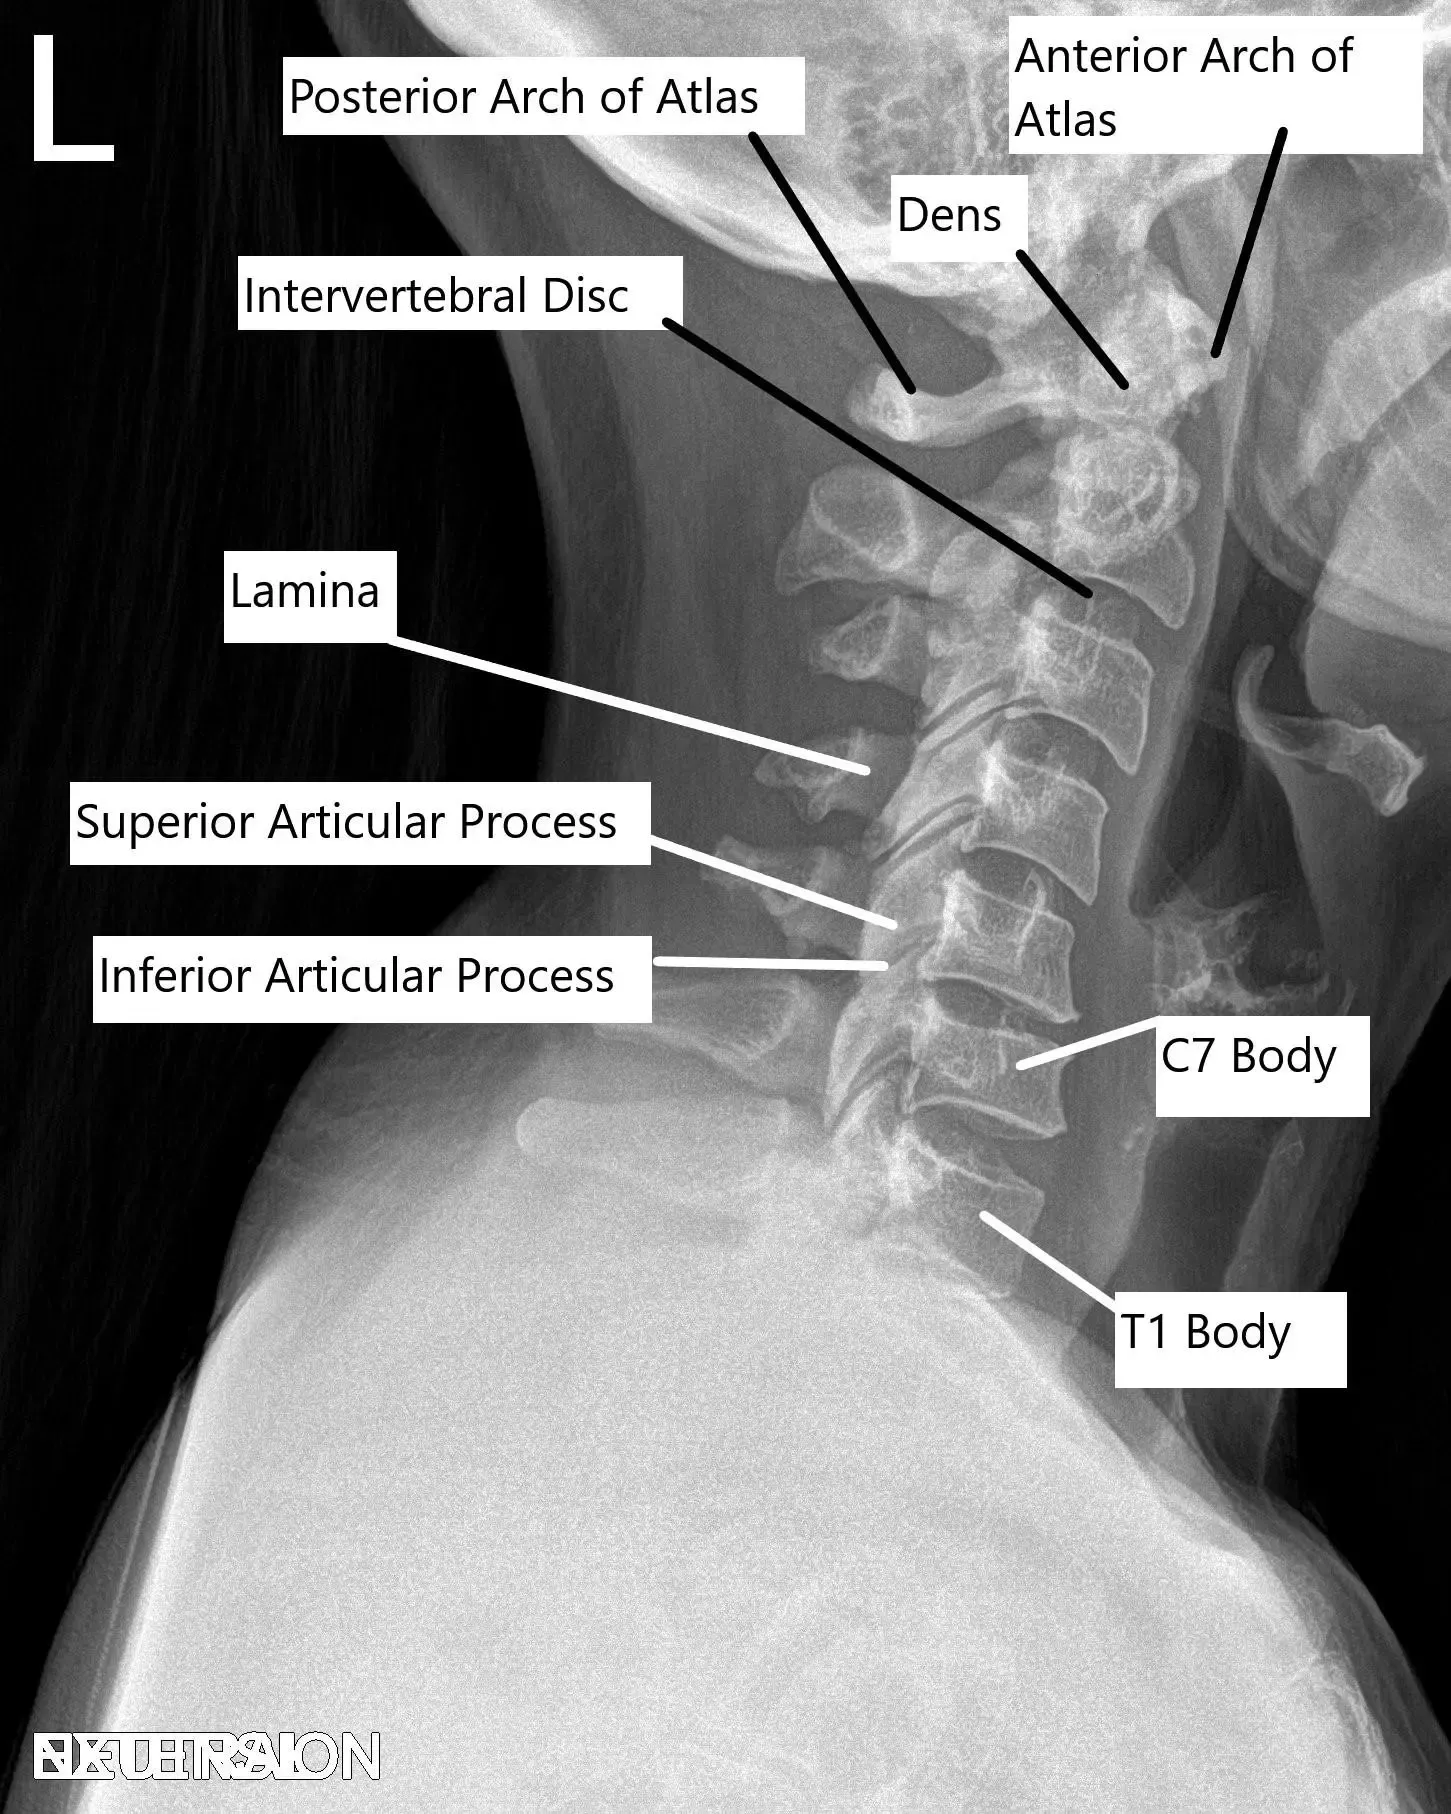

Radiografía de la columna cervical en vista lateral.

La columna cervical está compuesta por siete vértebras (C1 a C7), separadas por discos intervertebrales. Las vértebras protegen la médula espinal y permiten el movimiento en el cuello. El foramen, o pequeñas aberturas entre las vértebras, permite que los nervios espinales salgan de la médula espinal y viajen a diferentes partes del cuerpo. Cuando estas estructuras se ven comprometidas debido a cambios degenerativos, puede producirse compresión, lo que provoca dolor y otros síntomas neurológicos.